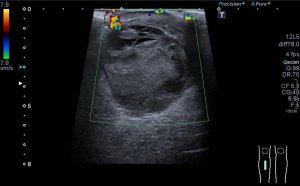

Lo que ves en estas imágenes que te voy a poner aquí son los hallazgos ecográficosque he podido visualizar hoy. Los voy a complementar con la correlación con las imágenes de TAC. En este caso específico con la eco solo se pudo corroborar los hallazgos del escáner, que a nivel anatómico arroja un mejor desarrollo de la anatomía regional implicada en el proceso.

6En el corte longitudinal de la imagen 1 ya se ve una vaso perimetrado por una imagen hiperecogénica, no compresible a la presión con la sonda convexa. En la imagen 2 con la sonda lineal se observa el enrejado habitual de los stents, que en otras ocasiones ya hemos comentado en otro post en localización distinta.